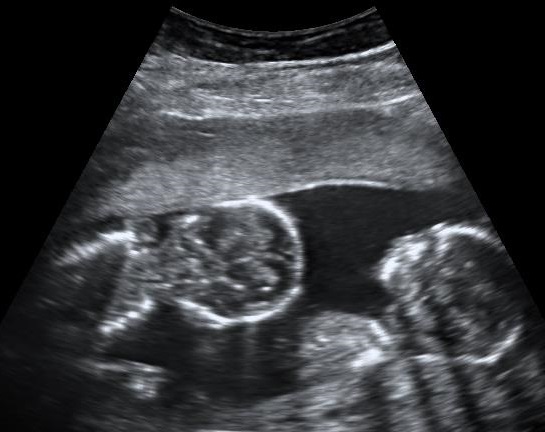

More And More Twins Are Being Born In The U.S.

In 2014, 33.9 sets of twins were born per 1,000 births in the United States, according to a new report on birth data from the Centers for Disease Control and Prevention. That’s a very slight increase from 2013, which saw a rate of 33.7 sets of twins per 1,000 births. But, more importantly, it’s the culmination of three decades’ worth of rising twin birth rates—in 1980, only 18.9 sets of twins were born per 1,000 births, according to the CDC. What’s causing the dramatic rise—and why doesn’t the same hold true for births of three or more, the rates for which are down 5 percent between 2013 and 2014?

Because of how IVF is done, multiple births, like twins or triplets, become more likely. If a couple is having trouble conceiving naturally, scientists can combine the parents’ extracted egg and sperm in the lab, then implant a fertilized embryo in the mother’s uterus. (More often than not, these embryos won’t take, so hopeful parents have to endure multiple rounds of expensive and emotionally exhausting procedures—the authors of a recent study in the Journal of the American Medical Association found that women were increasingly likely to conceive with each successive round of IVF, up until the ninth round.)

In each cycle, doctors commonly implant more than one embryo in the hope that at least one will be viable. That has caused a huge spike in multiple births—in 2011, 36 percent of all twins in the U.S. were born as a result of fertility treatments including IVF, as the Washington Post notes. And though doctors are now encouraged to implant no more than two embryos at a time to avoid problematic multiple births (remember Octomom?), and the rate of triplet births has dropped as a result, twins are still more likely to be born as a result of fertility treatments than from natural conception. In 2013, 1.5 percent of all children in the U.S. were born as a result of IVF.